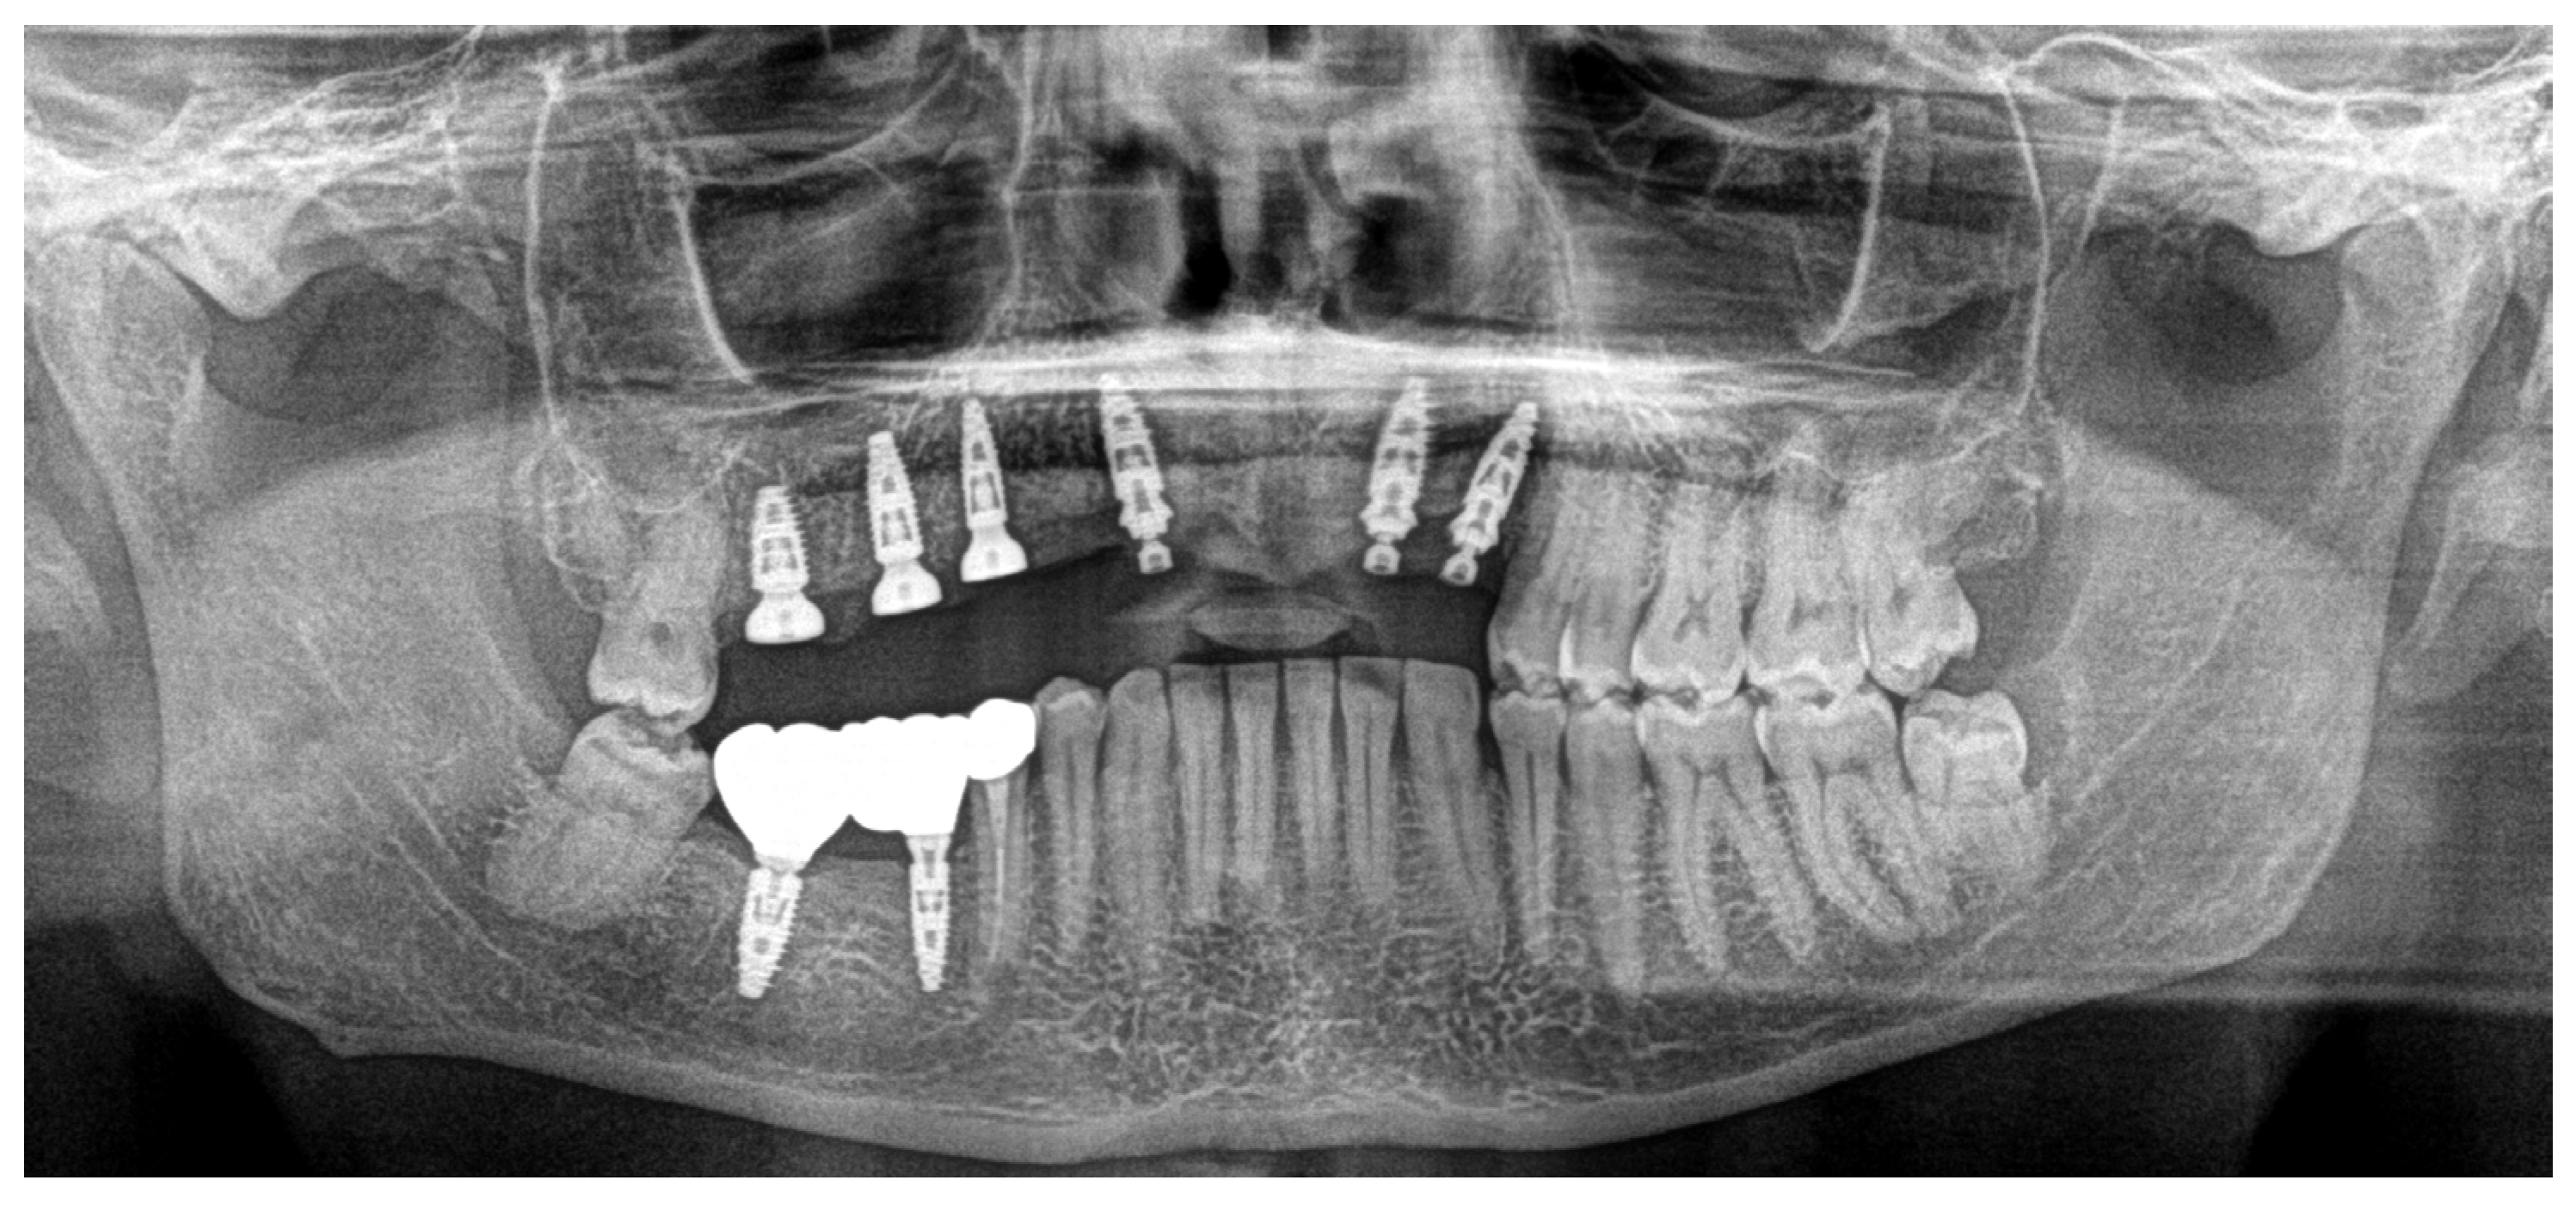

Based on previous experience and the speed of their development, in January 2023, it was decided to extract teeth 14 and 15, 46 and 47, decontaminating the alveoli, regenerating with PRF (in order to promote healing of the defect) and heterologous bone. So, the site was treated with a mix of Bio-Oss granules 25 (Geistilich Bio-Oss-Geistlich Pharma AG, Wolhusen, Switzerland), autologous bone chips, platelet-rich fibrin (PRF), and collagen membranes (45% Bio-Oss 25, 45% PRF, 10% autologous bone chips). Simultaneously, four implants (3.6 × 10 mm, Biotech Dental, Allée de Craponne, Salon de Provence, France) were inserted in the upper edentulous area, completely submerging them. However, an initial rejection of three of the four implants was observed (about 20 days after insertion), which made it necessary to remove them, decontaminate them with dye-free photodynamic therapy, and reinsert them 120 days later, when the implants were also inserted in areas 46-47 (3.6 × 10 mm and 4.2 × 10 mm, Biotech Dental, Allée de Craponne, Salon de Provence, France) in June 2023 (Figure 7).

In November 2023, teeth 16 and 17 were also extracted, always with the same surgical protocol of decontamination and photobiomodulation (Figure 8).

In June 2024, the implants were inserted in areas 16 and 17. Three months after the insertion of the last implants in 16-17 (4.2 × 10 mm and 4.2 × 8 mm, Biotech Dental, Allée de Craponne, Salon de Provence, France), it was possible to proceed with the digital impression-taking to proceed with a temporary prosthesis in PMMA (Figure 9) after a radiographic control (Figure 10).

Figure 7. Ortopantomography (OPT) post-surgery in September 2023.